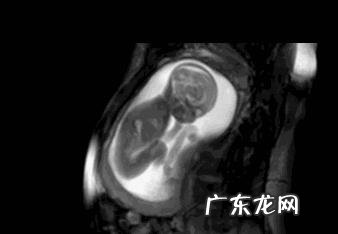

胎动的时候,胎儿在干吗呢?胎动一般从几个月开始明显?

在怀孕早期,宝妈孩感觉不到胎动,那是因为宝宝在子宫里的动作幅度太小,只有超声波才能观察到 。宝宝在妈妈子宫里,直到16周才能长到像妈妈紧握的拳头一般大,也是到了这个时候,宝宝开始调皮起来 。

宝宝长到四个月,在妈妈肚子里就会活跃起来,转头、转身、伸展、做鬼脸、打哈欠、咽口水等 。这时候的宝宝,在子宫里玩耍的很开心,睡醒了就会做运动,羊水保证了宝宝在里面旋转腾挪都不会有任何障碍,所以孕中期的宝宝在妈妈肚子里玩的最开心,也最活跃 。胎儿的胎动变得越来越有劲,也越来越有规律了 。

接近足月后,尤其是38周以后,宝宝在妈妈子宫里的活动渐渐变少,主要是宝宝长得太大了,子宫里可以旋转的空间变小,此刻超声波观察,,仅能看宝宝头部微小的活动、手脚四肢的活动也变少,呼吸运动更加规律 。

怀孕16周时,多数孕妈都会感觉到胎动了,少数孕妈还感觉不明显 。怀孕20周之后,胎动就开始变得明显多了 。

怀孕38周以后,胎儿长得很大了,子宫空间狭窄,加上好多宝宝已经完成了入盆,胎动幅度就会变小,大多是身体蠕动的动作 。